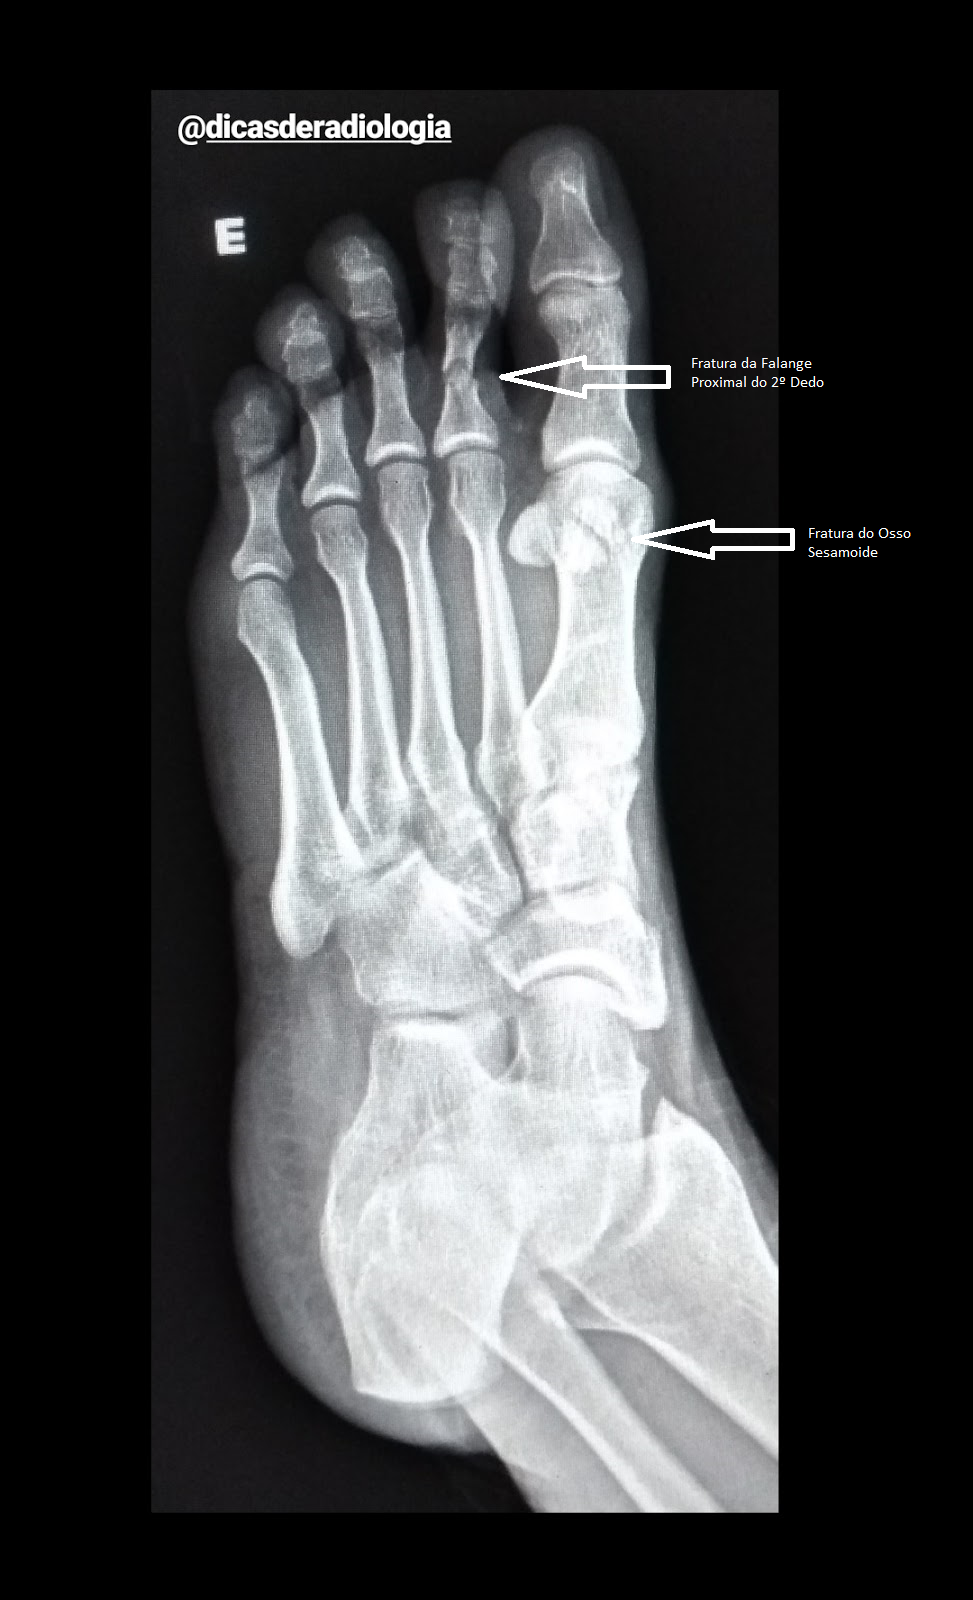

DICAS DE RADIOLOGIA - Tudo Sobre Radiologia: IMAGENS RADIOLÓGICAS

O tarso, o metatarso e as falanges. O tarso é a parte posterior do pé e inclui sete ossos, incluindo o calcâneo (osso do. Por exemplo, as fraturas podem variar de uma pequena fissura em um osso do pé, que passa facilmente despercebida, até uma fratura pélvica grave, que coloca a vida em. Como é o tratamento de cada tipo? Como o 5º pode ser quebrado? Entre as fraturas que acontecem nos metatarsos, a fratura do quinto metatarso é a mais. As fraturas do pé incluem fraturas nos dedos e fraturas nos ossos medianos do pé ( fraturas metatársicas ), nos dois ossos redondos pequenos na base. Você sabia que a fratura no pé é muito mais comum do que as pessoas costumam imaginar? O fato é que as fraturas dos ossos metatarsais são os. Foi um entorse ou uma fissura?